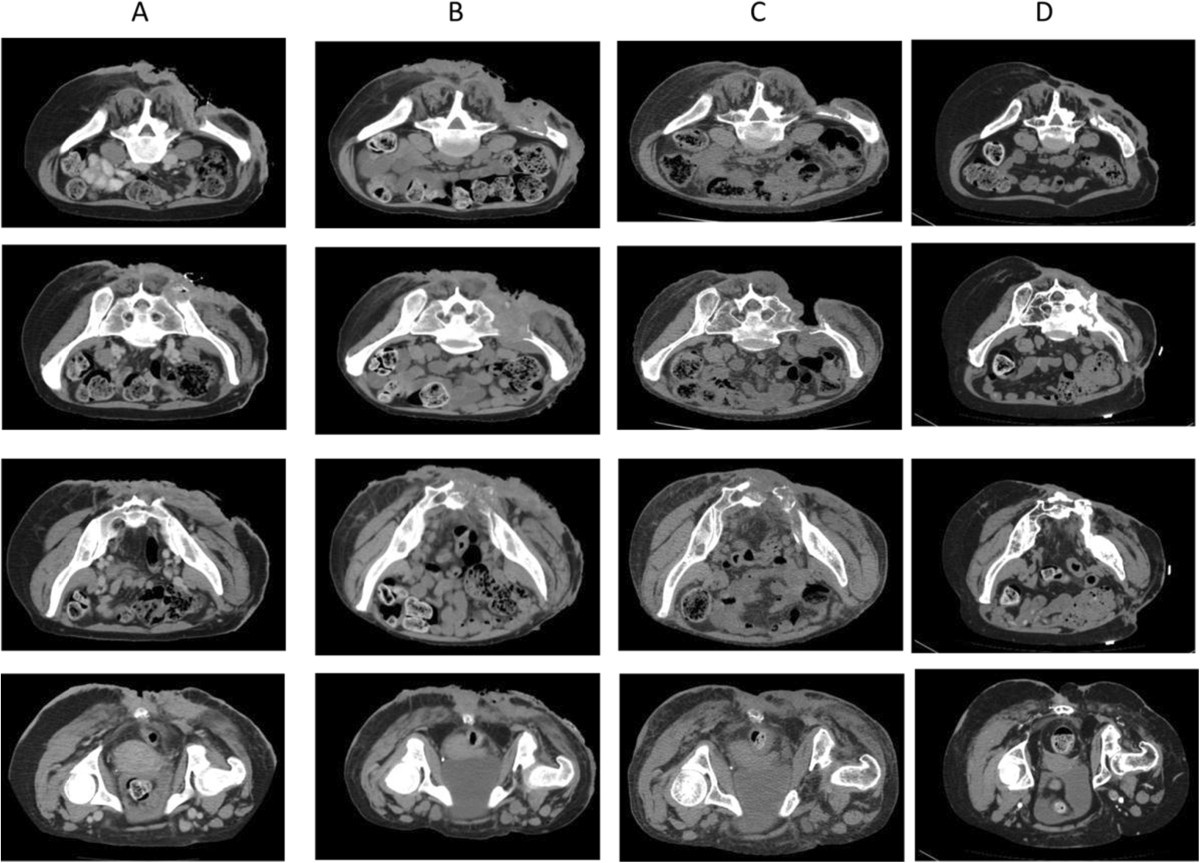

Figure 2From: Tomotherapy concomitant with cetuximab, followed by cetuximab as single-agent therapy for unresectable squamous cell carcinoma of the skin: a case report TC imaging: A baseline TC (December 2011); B simulation TC (March 2012); C follow up (June 2013); D last follow up (February 2014). Back to article page